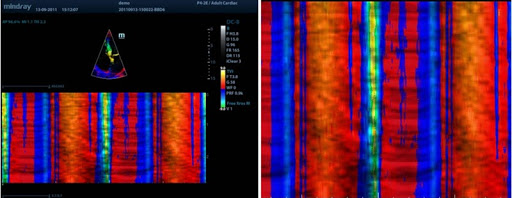

Free Xros M

Анатомический М-режим. Дает возможность выполнять точные анатомические измерения при помощи свободного размещения линий М-режима под любым углом. Получение большего количества диагностической информации за счет одновременного использования до 3 линий М-режима.

Free Xros CM

Огибающий (нелинейный) анатомический М-режим. Позволяет получать полную информацию о движении сердечной мышцы на различных фазах и одновременно определять степень синхронизации миокарда. Точность результатов обеспечивается высокой частотой кадров.

Тканевая допплеровская визуализация (TDI)

С помощью тканевой допплеровской визуализации можно определять количественные показатели движения и функционирования сердечной мышцы, используя режимы полной визуализации для быстрой и непосредственной диагностики.